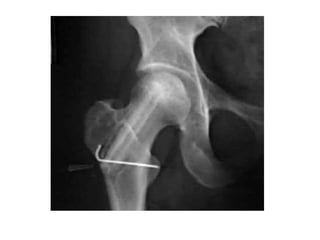

THR in failed hip fracture surgery

• Prolong non ambulatory patients due to

failed hip surgery.

• Dislocations and failure

• High mortality.

• In trochanteric nonunions, length of the

femur cannot be restored with a standard

implants.

• Calcar replacement stem.